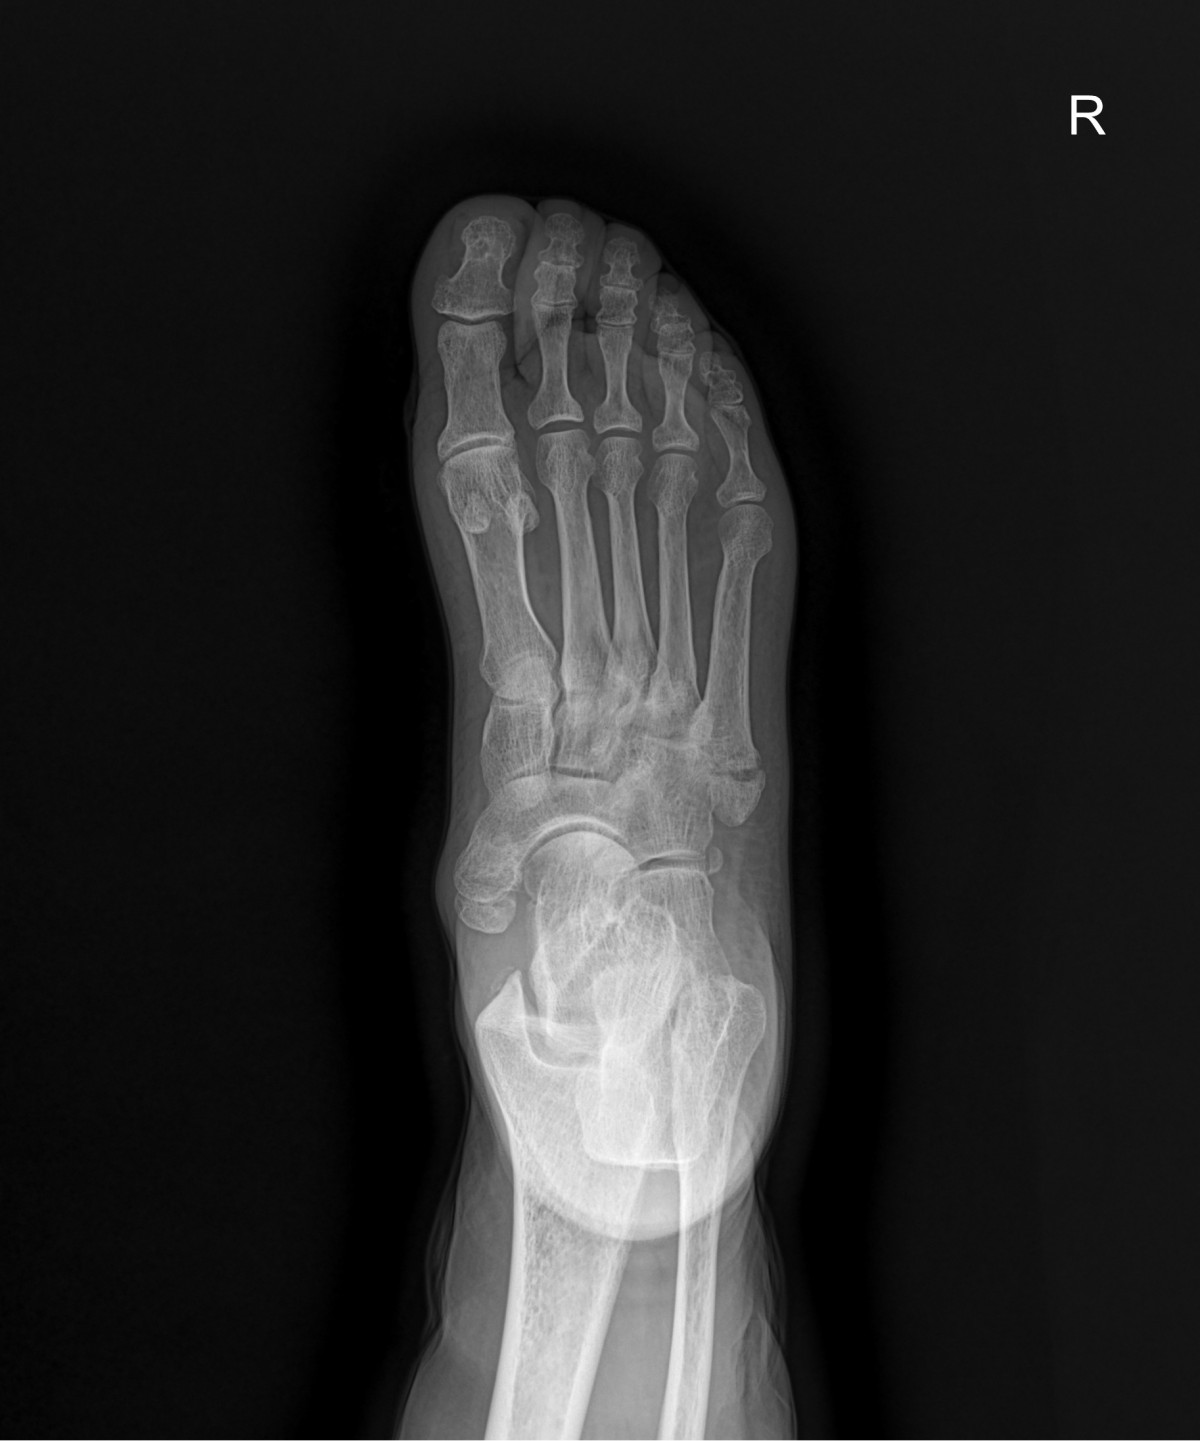

정지영원장님 발등 골절 수술 양순O 환자

dae765e4d9ac96aee867c9d6292d8784_1758008317_1639.jpg